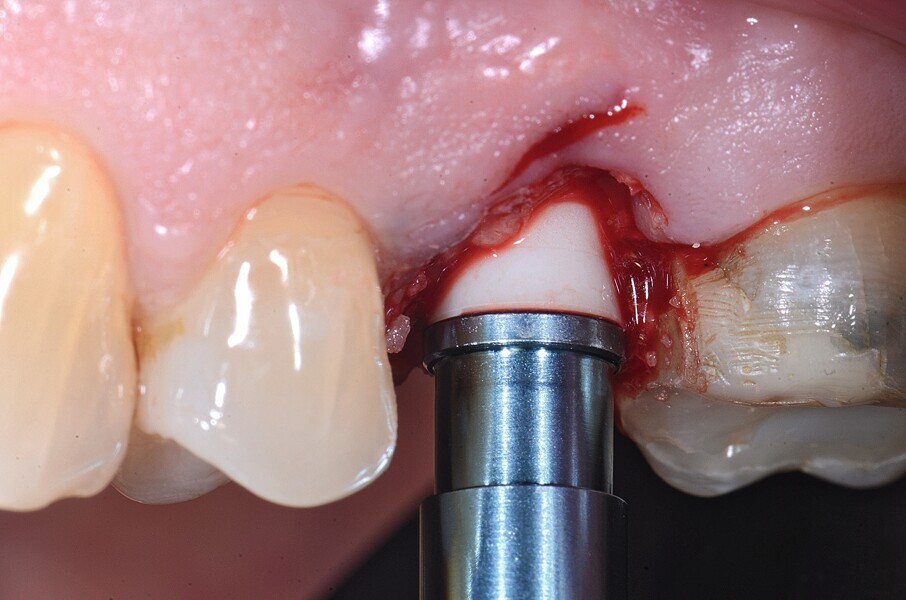

Fig. 15 : Extraction atraumatique.

La pose immédiate d’un implant deux pièces en céramique au niveau tissulaire a été accomplie tout en préservant l’alvéole (allogreffe constituée d’un substitut osseux et protection par une membrane de collagène résorbable). La mise en charge n’a pas été réalisée à ce stade (Figs. 12–24)